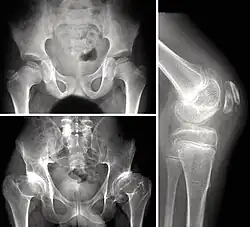

Children with autosomal dominant MED experience joint pain and fatigue after exercising. Their x-rays show small and irregular ossification centers, most apparent in the hips and knees. There are very small capital femoral epiphyses and hypoplastic, poorly formed acetabular roofs.[1] A waddling gait may develop. Knees have metaphyseal widening and irregularity while hands have brachydactyly (short fingers) and proximal metacarpal rounding. Flat feet are very common.[2] The spine is normal but may have a few irregularities, such as scoliosis.

By adulthood, people with MED are of short stature or in the low range of normal and have short limbs relative to their trunks. Frequently, movement becomes limited at the major joints, especially at the elbows and hips. However, loose knee and finger joints can occur. Signs of osteoarthritis usually begin in early adulthood.[3]